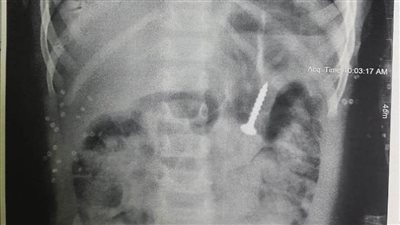

استخراج "مسمار" من معدة طفلة بمستشفى المنصورة التخصصي